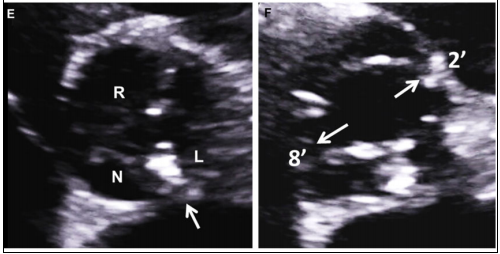

正常主动脉瓣由3个半月瓣组成,称三叶式主动脉瓣(tricuspid aortic valve, TAV),根据瓣膜位置及冠状动脉开口可将其分为左、右和无冠状动脉瓣。而BAV因主动脉瓣发育异常导致相邻两个半月瓣形成融合瓣,部分融合瓣上可见融合嵴,使瓣叶不对称。

Sievers分型

Sievers分型广泛应用于临床,根据融合嵴的数量将BAV分为3型:Type 0型(无嵴)、TypeⅠ型(1个嵴)和TypeⅡ型(2个嵴),其中最常见的是TypeⅠ型,约占90%。根据嵴的空间位置又分为左右冠窦融合型(RL型)、右无冠窦融合型(RN型)、左无冠窦融合型(LN型),其中RL型最常见,约占80%。

最新国际共识认为仅基于外科角度的Sievers分型仍有局限性,因此新的分型为:融合型、双窦型和部分融合型。其中融合型最常见,占90%~95%,相当于TypeⅠ型。双窦型BAV并不常见,占5%~7%,由大小、形状大致相同的两个瓣叶构成,分前侧对侧表型和前后表型(图b)。部分融合型的流行率尚不清楚,表现为典型的三叶瓣膜,但在连合底部可见<50%的瓣尖融合。至于Sievers分型中的Type Ⅱ型,共识认为称单叶瓣较为合适。

融合型

R-L

R-N